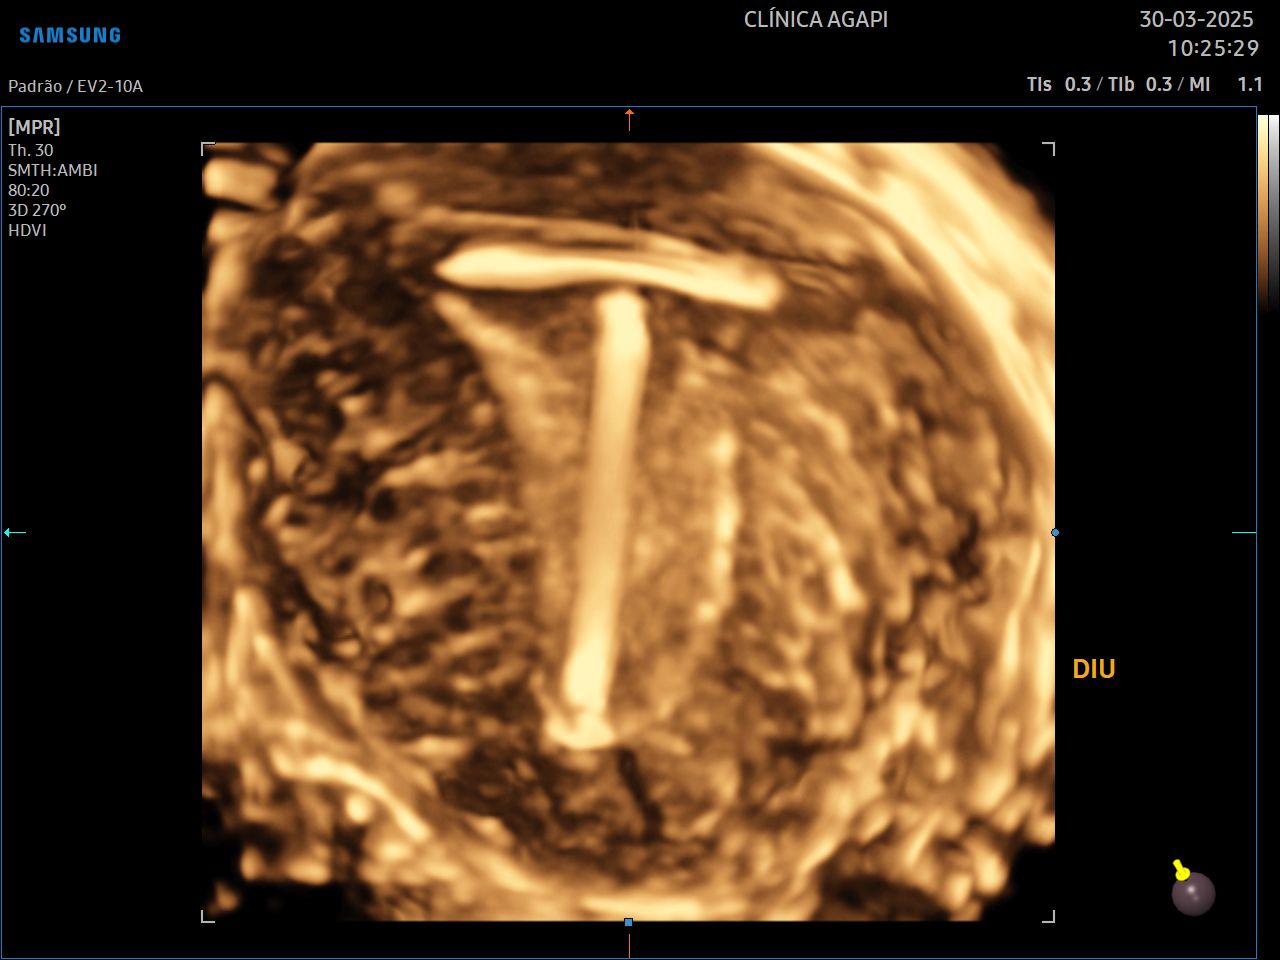

Ultrassonografia Ginecológica 3D/4D

Exame complementar à ultrassonografia transvaginal comum, que auxilia no diagnóstico de algumas malformações uterinas.